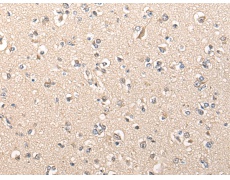

IHC positive control: |

Human brain and human liver cancer |